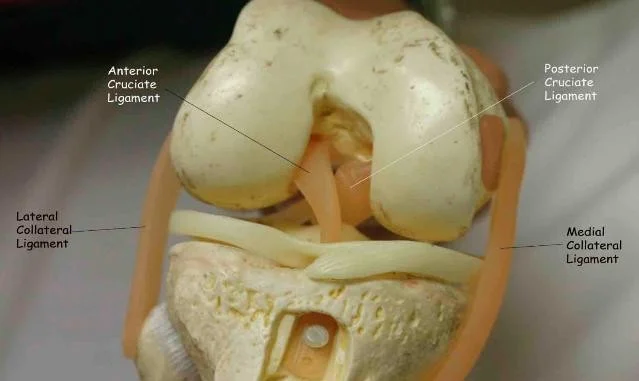

Ligament Tests

- Collateral ligaments: Medial / Lateral

- Cruciate ligaments: Anterior / Posterior

Collateral Ligament Testing

Cruciate Ligament Testing

- Anterior/Posterior Drawer Test

- Lachman’s test

- Sagging sign: indicates Posterior cruciate ligament tear